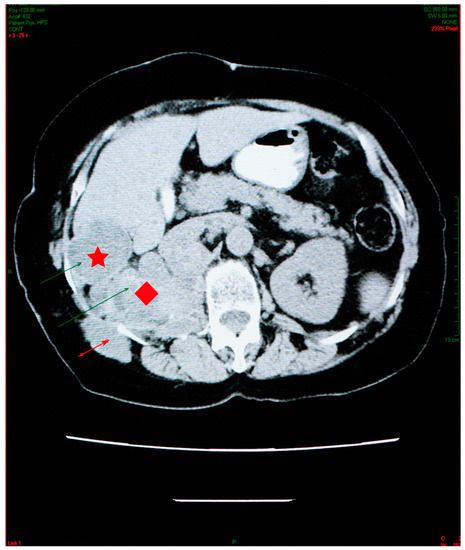

A favorable evolution of the cysts under antiparasitic treatment was observed in October 2009 and March 2010 (Figure 4).

The abdominal CT scan showed multiple spontaneous hypodense masses with hyperdense borders, occupying the entire kidney space, with no evidence for the right kidney (Figure 6).

The maximum axial dimension of the above-mentioned lesions was 10 cm, which is considerably less than what was recorded in 2006. In addition, this conglomerate of hypodense images was remarked to have increased in overall density. The conglomerate presented cranial and caudal extension, starting just beneath the diaphragm and ending right under the plane of the renal artery, with a close anatomic relation to the right diaphragm pillar, right hemidiaphragm, and right psoas muscle. The spontaneous hypodense, heterogenous mass, with an axial maximum diameter of 46 mm, located in the VI liver segment, appeared to be reduced in comparison to the 2006 examination.

Figure 6. Abdominal CT shows reduction in the aspect and dimensions of the cysts—right kidney space (red diamond), the sixth right liver segment (star) and in the right iliac fossa and right paravertebral area (arrow)—associated with favorable evolution under treatment.